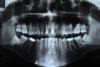

komar86 Опубликовано 4 августа, 2012 Автор Поделиться Опубликовано 4 августа, 2012 (изменено) Да была травма и проводилось лечение. С тех времен прошло около 9-10 лет, но лечились они не зразу после травмы, а спустя 3-5 года, когда уже успели изменить свой цвет. Вот панорамный снимок (дата снимка 19.07.2012): Изменено 4 августа, 2012 пользователем komar86 Ссылка на комментарий